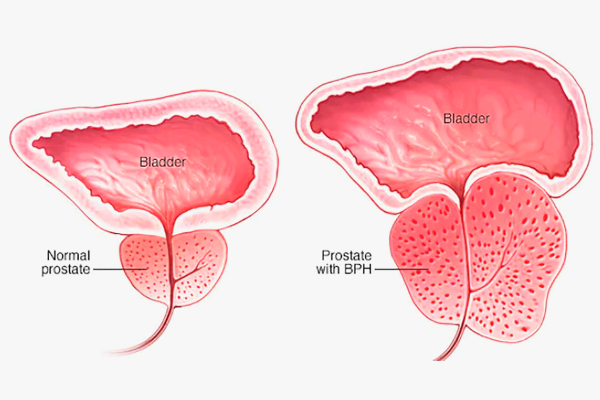

The most common prostate issue that men will be forced to reckon with (to some extent) is a condition known as benign prostatic hyperplasia (BPH).

BPH is a non-cancerous condition in which the prostate gland becomes enlarged. The prostate is a small gland located just below the bladder in men. As the prostate enlarges, it can press against the urethra (the tube that carries urine out of the body). This can cause urinary symptoms such as difficulty starting to urinate, a weak urine stream and the need to urinate frequently, especially at night.

The exact cause of BPH is unknown, but it is believed to be related to changes in hormone levels as men age. The prostate gland contains cells that respond to the male hormone testosterone. As men age, testosterone levels in their bodies decrease, but another hormone called dihydrotestosterone (DHT) levels remain the same. DHT causes prostate cells to grow and divide, leading to an enlarged prostate.

Symptoms of BPH and Other Issues

As stated previously, BPH is a condition that causes the prostate gland to become excessively enlarged. While this may seem trivial at face value, it’s a condition that can lead to many problems. The prostate is a small gland located below the bladder in men and as it enlarges, it can press against the urethra (the tube that carries urine out of the body) and cause urinary symptoms.

- Difficulty starting to urinate: As the prostate enlarges, it can put pressure on the urethra and make it difficult to start urinating.

- Weak Urine Stream: As the prostate enlarges, it can also put pressure on the urethra and make it challenging to maintain a strong urine stream.

- Frequent Urination: As the prostate enlarges, it can also pressure the bladder.

- Urgency: A sudden and intense need to urinate that can’t be delayed.

- Incontinence: Leakage of urine or difficulty controlling urination.

- Interrupted Flow: Starting and stopping while urinating.

- Incomplete Emptying: Unable to empty the bladder (trust and believe that this is one of the worst symptoms you can suffer from on this list because you’ll be left feeling as though you contracted an STD as if you’re back in college again!)

- Straining: The need to push or bear down to urinate.